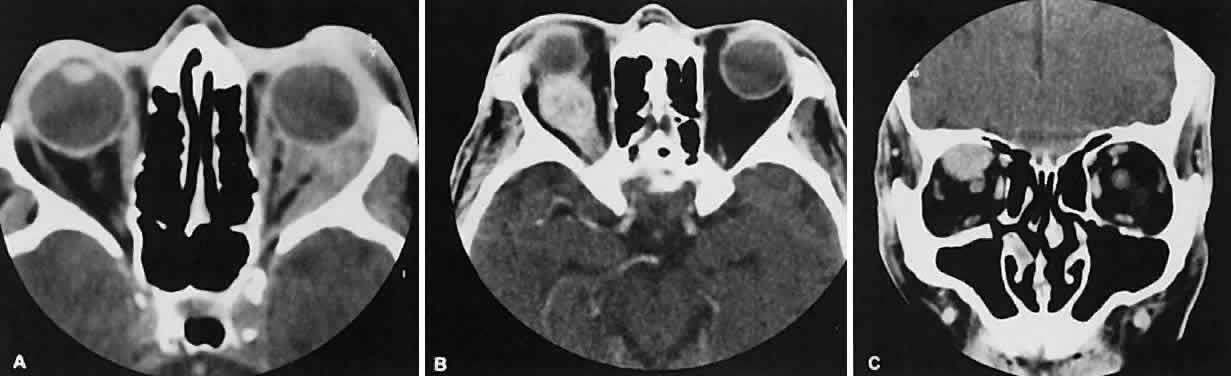

Radiographic evaluation can show either infiltrative or circumscribed masses. Some tumors display a predilection for metastasizing to certain structures, such as prostate carcinoma to bone and cutaneous melanoma to EOMs (Fig. 21). Evidence of bilateral disease at presentation ranges from 7% to 9%, with the prime example being neuroblastoma.71

Fig. 21. A. Axial view shows bilateral involvement from metastatic breast carcinoma. An amorphous infiltrative soft-tissue mass is more apparent in the right orbit, which encases the globe, producing clinical and radiographic enophthalmos. Cutaneous melanoma metastatic to the superior rectus muscle is depicted on axial (B) and coronal (C) views. A locally enhancing and asymmetric enlargement is restricted to the right superior rectus muscle. These features distinguish this lesion from Graves' orbitopathy.